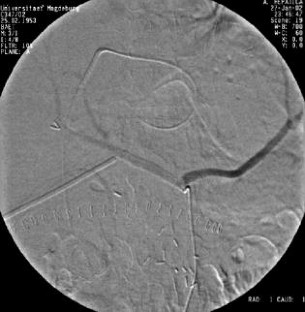

Wir berichten über das diagnostische und therapeutische Vorgehen anhand von 7 Patienten mit Blutungen aus der A. gastroduodenalis (n=5) nach pankreaschirurgischen Interventionen bei Pankreaskopfkarzinom, Rezidiv eines Liposarkoms und chronischer Pankreatitis, der A. hepatica communis (n=1) bei chronischer Pankreatitis und der A. mesenterica superior (n=1) nach akuter Pankreatitis. Anhand von 4 Kasuistiken werden unsere Erfahrungen mit der Implantation von Stentgrafts (Hemobahn®-Prothesen) vermittelt. Den Vorteil der Stentgrafts sehen wir in der sofortigen Blutstillung bei fehlendem Kontakt der Endoprothese zu infiziertem Gewebe und Erhalt der Perfusion des abhängigen Organs. Unsere positiven Erfahrungen mit diesen interventionellen Therapieverfahren erfordern jedoch weitere klinische Untersuchungen, wobei im Mittelpunkt die Indikationen, die technische Erfolgsrate, die stentbedingten Komplikationen und die Langzeitverläufe stehen sollten.

Spontaneous or postoperative hemorrhage into the abdominal cavity due to inflammatory vessel arrosion represents an uncommon but menacing situation. According to the literature, such hemorrhage is associated with a lethality of nearly 2%. Therapeutical options include reoperation and interventional radiological techniques such as endovascular catheter techniques with stent graft implantation or the embolization of vessels. We report on the management of seven cases with hemorrhage either from the gastroduodenal artery (n=5) following pancreatic surgery for pancreatic carcinoma, liposarcoma, and chronic pancreatitis or from the common hepatic artery (n=1) and the superior mesenteric artery (n=1) following chronic pancreatitis. The present article describes our experiences with stent graft implantation (hemobahn prosthesis) in four cases. Based on these experiences, we see the advantages of stent grafts in primary hemostasis without any contact to infected tissue and the preservation of regular perfusion. However, further clinical data are required focussing on indication, technical success rates, stent-related complications, and long-term outcome.